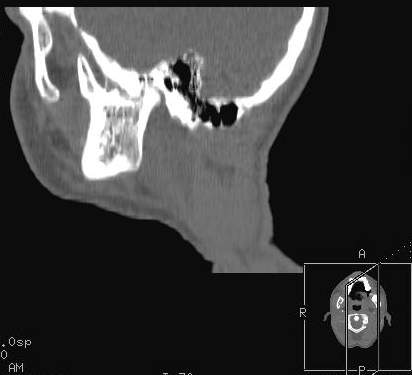

Пациент В., 13 лет. Диагноз: Костный анкилоз левого височно-нижнечелюстного сустава (ВНЧС), левосторонняя микрогения. Болеет с 2-х летнего возраста. Возможная причина развития анкилоза – воспалительный процесс (в первые 1,5 года жизни часто болел простудными заболеваниями, травму родители отрицают). В 3 и 5 лет проводилась редрессация – безуспешно.Прилагаются: ортопантомограмма, кадры СКТ с 3Д реконструкцией. Вопросы: определение тактики лечения – вид и сроки реконструктивно-пластической операции (этапов операции), а именно – неоартропластики и устранения микрогении, медикаментозная терапия в до- и послеоперационный период, ортодонтическое лечение.